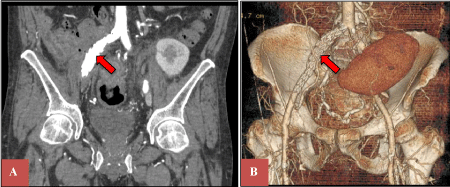

Our patient is a 49-year-old male with a long history of insulin-dependent diabetes mellitus (IDDM) complicated by diabetic nephropathy and end-stage renal disease (ESRD) on hemodialysis. After a standard preoperative pre-transplant process, he was found to have a matched cadaveric donor and underwent a combined kidney and pancreas transplant. The pancreatic graft was enterically drained and the kidney was placed in the left lower abdomen in the traditional manner. The first two weeks of postoperative course were complicated by pancreatic graft thrombosis and ureteral leak, requiring pancreatectomy, right common iliac artery repair with a bovine patch, and repair of the ureteral leak with nephrostomy tube placement. After being discharged from the hospital, he had a slow recovery, requiring close monitoring and frequent follow up appointments. Fourteen months after the initial surgery, he presented to the emergency room complaining of abdominal pain after a fall. Due to concern of organ damage from blunt trauma to the abdomen, a computerized tomography scan (CT) of the abdomen and pelvis with intravenous contrast was performed which showed a pseudoaneurysm arising off the right common iliac artery with free pelvic fluid concerning for an associated leak (Figure 1). There was also demarcation of the sigmoid colon with contrast despite the lack of administration of oral contrast. No definitive fistulous tract was seen; however, an arterio-enteric fistula was highly suspected based on the history of the arterial wall patch repair. The patient remained hemodynamically stable without evidence of gastrointestinal bleeding. Vascular surgery was consulted, and an emergency retrograde pelvic angiogram and aortogram was performed through an ipsilateral catheterization of right external iliac artery. Identification of a pseudoaneurysm adjacent to the repair of the right common iliac artery raised concern of a pressure-erosion mechanism for the creation of the arterio-colonic fistula, which at the time was not involving all the layers of the bowel wall, but instead dissecting through the sigmoid colon wall. Because of these particular findings of the fistula, with partial colonic wall involvement, the decision was made to place an intravascular stent graft to cover the area of connection between the pseudoaneurysm and the sigmoid colon. An exclusion stent graft was deployed in the right common iliac/external iliac artery pseudoaneurysm, utilizing the same system used for the endovascular treatment of infrarenal abdominal aortic or aortoiliac aneurysms (Endurant II® contralateral limb stent graft; 16 × 10 × 156 mm - Medtronic) as shown in Figure 2. This procedure was performed as a temporary control measure, to decrease the possibilities of a massive lower gastrointestinal bleeding. Although a true communication with the colonic mucosa and bowel lumen was not proven, the likelihood of graft infection was assumed to be high, therefore, once having a better control of the fistula, the plan was to proceed with definitive surgical repair in the near future.

Figure 2: Placement of an exclusion stent graft in the right common and external iliac arteries. View Figure 2